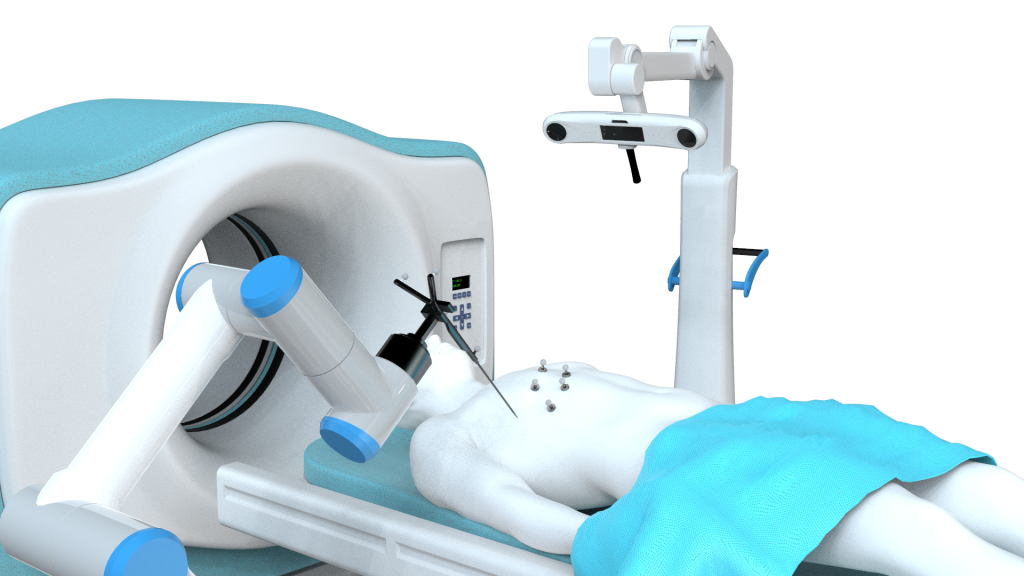

Gmedisys’s proprietary software suite powers seamless workflow integration:

3D Reconstruction & Image Segmentation: Transforms 2D imaging (CT/MRI) into detailed 3D models for preoperative planning.

Spatial Registration: Aligns preoperative images with real-time surgical space via pointer or laser registration, ensuring sub-millimeter alignment.

Robot Calibration: Uses multi-loop algorithms and Kalman filtering to calibrate robotic arm coordinate systems, optimizing precision.

Surgical Navigation Interface: Intuitive, real-time visualization of instrument positions relative to anatomy, supporting decision-making during procedures.